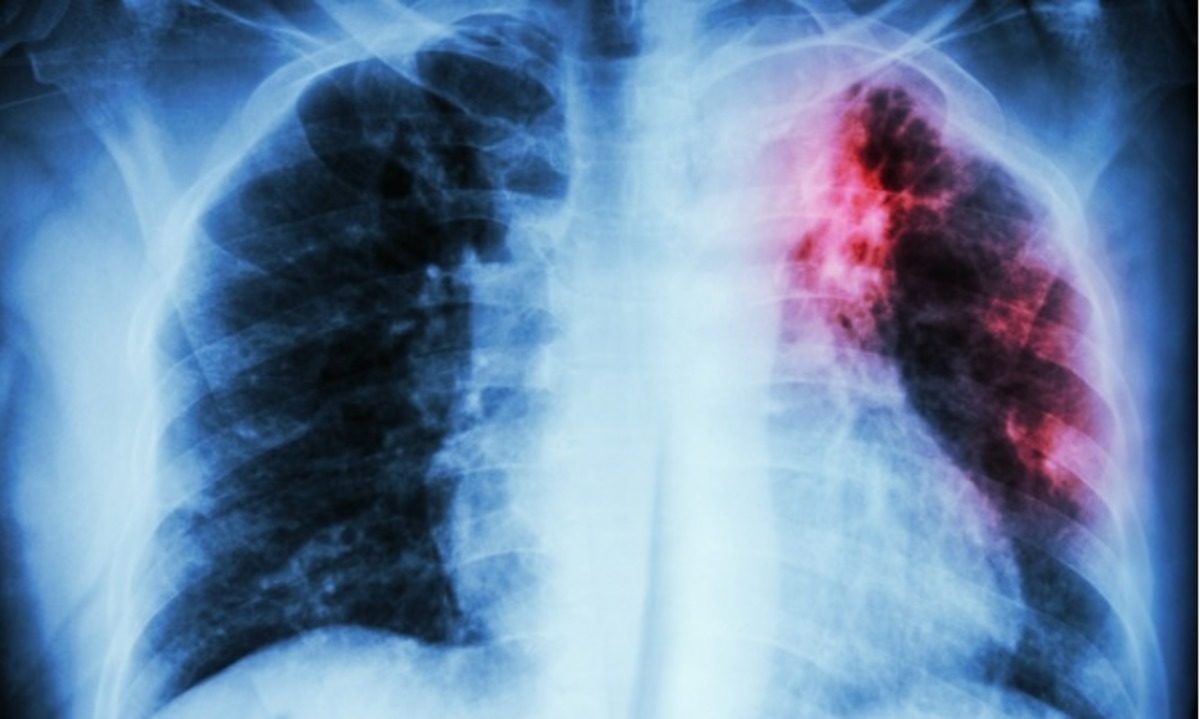

Παγκόσμια Ημέρα Φυματίωσης 2018: Τι είναι και πώς εκδηλώνεται η φυματίωση

Τα βακτήρια της φυματίωσης συνηθέστερα αναπτύσσονται στους πνεύμονες και μπορεί να προκαλέσουν συμπτώματα όπως: